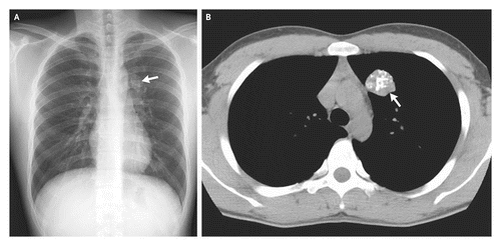

Пример: объемное образование левого легкого — гамартома. Кальцинация в виде «попкорна».